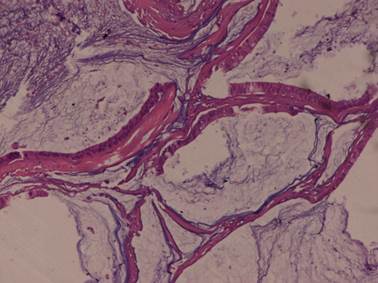

The operated specimen was encapsulated, solid and cystic with visible areas of capsular breach, of size 21 × 18 × 7 cm, and encased the upper pole and the middle region of the kidney. Perirenal fat and Gerota’s fascia were not involved. Microscopically, the tumour consisted of elongated, anastomosing tubules separated by lakes of mucin from a prominent spindle cell area. The tubules were composed of low cuboidal cells with amphophilic to eosinophilic cytoplasm with mild anisonucleosis. Foci of SD comprising about 30% of the tumour were seen, with pleomorphic low-grade nuclei. No lymphovascular invasion was noted (Figures 1 and 2). Alcian blue stain showed the typical blue-coloured mucin in the stroma between the tubules and the cords (Figure 3). The tumour cells were diffusely positive for cytokeratin 7 (Figure 4), EMA and vimentin but negative for CD10. Six cycles of adjuvant chemotherapy (vincristine, Adriamycin and cyclophosphamide [VAC] regimen), comprising cisplatin 50 mg/m2, vincristine 1.0 mg/m2, Adriamycin 40 mg/m2/day (Dako, Germany), cyclophosphamide 1000 mg/m2 and actinomycin-D 0.5 mg/m2 followed by 50 Gy/25 fractions of cobalt-60 teletherapy were given. The patient tolerated the therapy well without any appreciable adverse effects and unremarkable blood chemistry findings. Follow-up after 12 months demonstrated that the patient was doing well with no evidence of recurrence or metastasis.

Figure 2. MTSCC: Foci of sarcomatoid differentiation were seen with pleomorphic high-grade nuclei without any evidence of vascular invasion. Haematoxylin and eosin, 40×.